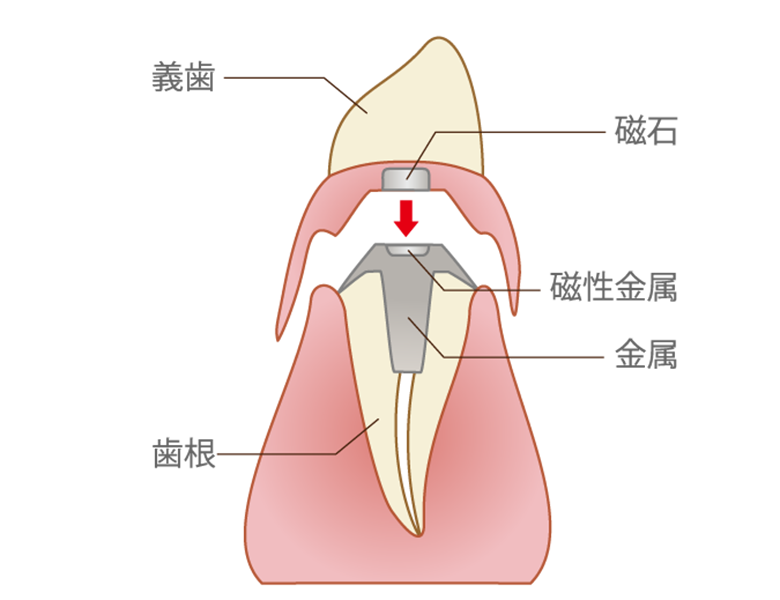

アタッチメント義歯(精密接合装置)

磁石(マグネット)や、精密なボタン状の装置(ロケーターなど)を利用して固定します。

強力な固定と簡単な着脱

外からは装置が見えないため非常にスマートです。強力に固定されるため、食事中に外れる心配がありません。

お手入れのしやすさ

複雑なバネがないため、残っている歯のブラッシングがしやすく、清潔な口腔環境を保ちやすいのがメリットです。